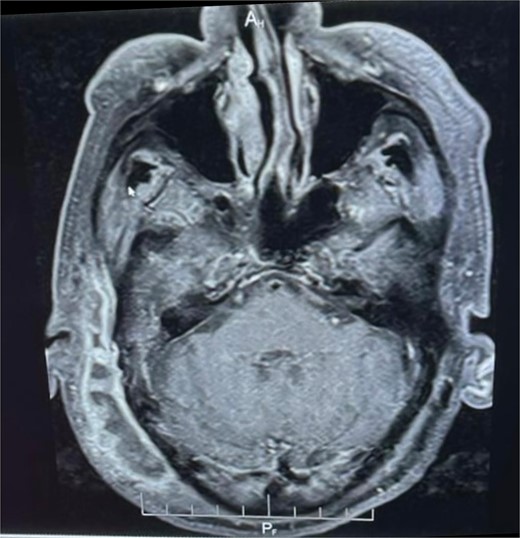

Brain magnetic resonance imaging (MRI) demonstrated diffuse skin and subcutaneous tissue oedema involving the right temporoparietal and occipital regions, with multiloculated subcutaneous fluid collections displaying marginal contrast enhancement. Additionally, there was evident heterogeneous signal enhancement extending into the right external auditory canal, indicative of inflammatory changes. A smaller, marginally enhanced fluid collection was observed along the petrous apex in the right nasopharynx, suggestive of an abscess or localized infection (Fig. 1).

Enhanced MRI: Muitiloculated subcutaneous collection at the right temporoparietal region with marginal contrast enhancement, measuring ~0 cm x 2 cm. Marginally enhanced fluid collection on the right medial aspect of the nasopharynx.

Our case’s MRI revealed diffuse skin and subcutaneous tissue oedema involving the right temporoparietal and occipital regions, as well as multiloculated subcutaneous fluid collections with marginal contrast enhancement. Furthermore, there was clearly heterogeneous signal enhancement extending into the right external auditory canal, indicating inflammatory changes. A smaller, marginally enhanced fluid collection was observed in the right nasopharynx along the petrous apex, indicating an abscess or localized infection. CT petrous temporal bone is useful in determining bone erosion in NOE, while MRI shows soft tissue extent, though these changes may be absent in early NOE [11]. The sensitivity of MRI for diabetic osteomyelitis is 90% and the specificity is 79% [11]. High-resolution imaging, such as MRI and computed tomography (CT), can help to determine the extent of inflammation in the petrous bone and surrounding structures. However, determining the response to treatment is difficult because inflammation-related tissue changes are visible by both modalities for a long time after the active inflammation has subsided [9]. Because there are no agreed-upon criteria for diagnosing NOE, clinical, radiological, and biological arguments must be used to maintain NOE diagnosis [13].